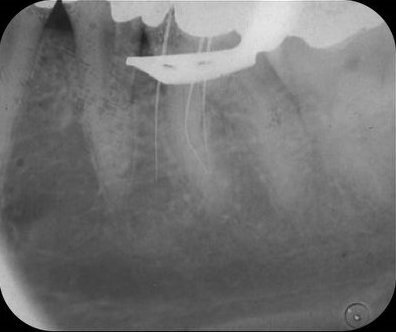

Tijdens het zoeken van de kanaalingangen met een ronde boor veroorzaakte ik een perforatie naar mesiaal (afb. 2), die zichtbaar werd nadat ik een lengtefoto had genomen, waarbij een vijl door de mesiale begrenzing van de mesiale radix stak.

Afb. 2: Lengtefoto van de mesiale kanalen, waarbij een handvijl in de perforatie steekt